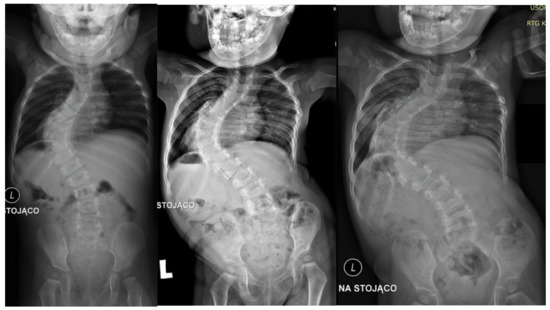

A 2-year-old girl was admitted to our clinic with rapidly progressive thoracic scoliosis. Previously, the patient had undergone conservative treatment with a brace and physical therapy. The patient had no other disorders. The major curve of the thoracic spine Cobb angle was 70° at 16 months of age, 100° at 22 months, and 122° at 30 months (Figure 1).

Figure 1.

Showed standing: (from left to right) AP X-rays at 16 months old (70 degrees), 22 months old (100 degrees), and 30 months old (122 degrees).